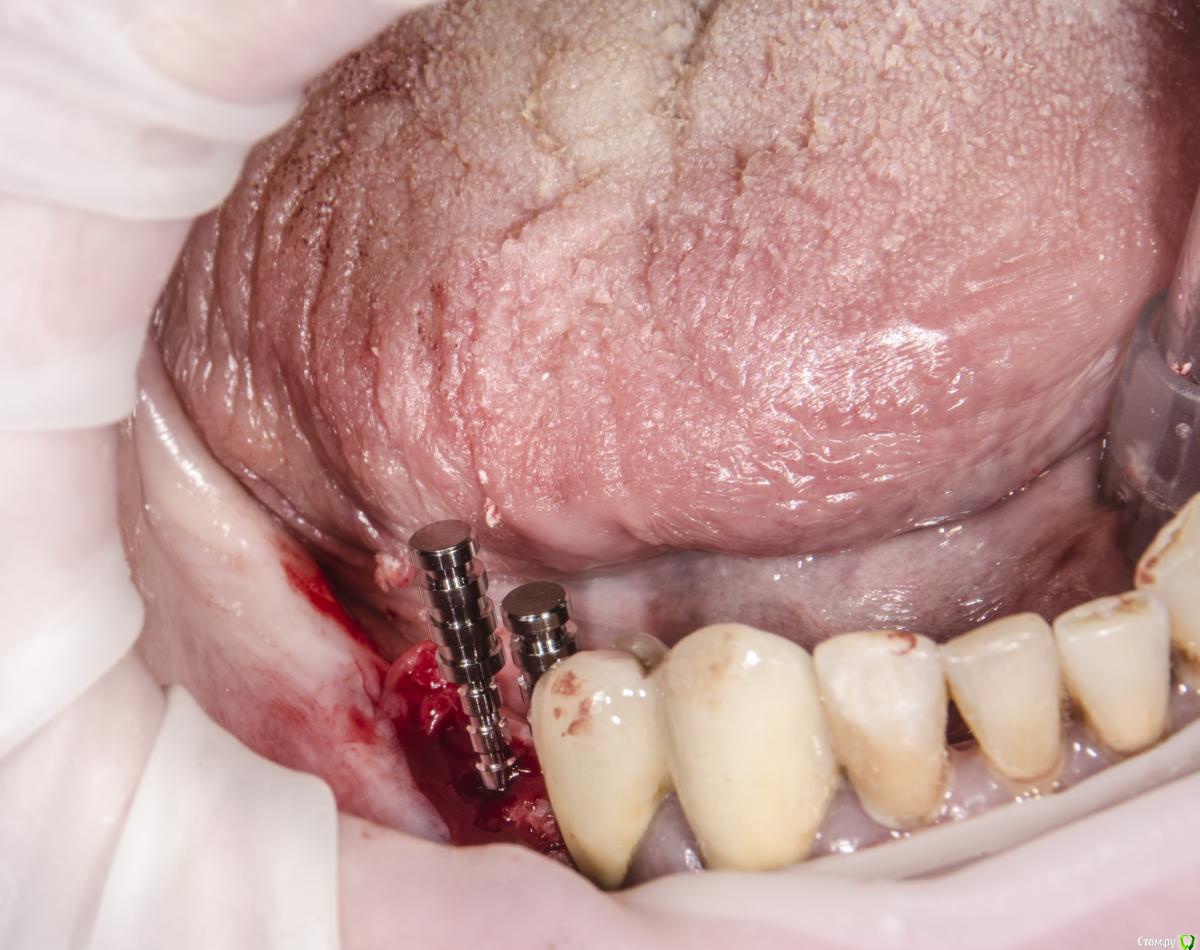

kamranchick Опубликовано 12 сентября, 2015 Поделиться Опубликовано 12 сентября, 2015 Доброго всем дня и хороших выходных)вопрос следующего планаПациент обратился с жалобами на отсутствие зубов пациент среднего достатка.начали потихоньку работать, сверху все зубы удалили, начали имплантирование снизув области 4 сегмента установили 2 имплантата в области 45 46, так как условия неплохие, в области 7 зуба начинается скос, ну и придется либо заваливать имплантат язычно либо делать пластику, как Вы думаетестоит ли вкручивать имплантат в область 7 зуба?тогда наверное и с другой стороны придется вкручивать, так как там отсутствует 4567зуб, ну а сверху как вы поняли зубов нету уже, ни одного)кт если кому то понадобятся. срезу кину в в в будние дни) Ссылка на комментарий

Magomed Опубликовано 13 сентября, 2015 Поделиться Опубликовано 13 сентября, 2015 завалите язычно, для чего придумали угловые абатменты. Ссылка на комментарий